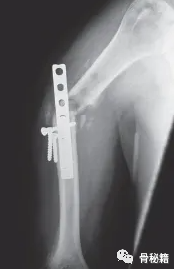

锁定螺钉难以取出时怎么处理?

1反螺纹钻

2没头的钉子怎么处理

3断的钉子怎么处理

下次拧入锁定螺钉的时候适可而止。